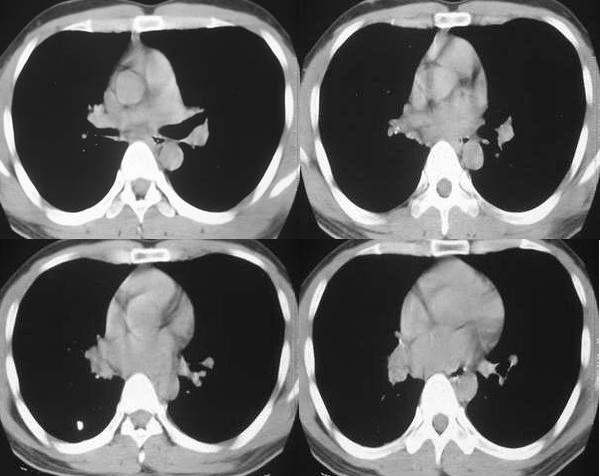

男,28岁,右胸不适,轻咳.余无特殊症状.请各位大侠发表见解

右肺门区软组织肿块,边缘钙化,右肺中叶不张,右下叶背段结节状及斑片状影。首先考虑结核,建议支气管镜检查排除其他。

支持结核伴中间段支气管内膜结核、中叶肺不张。

右侧中间段支气管管壁增厚,管腔狭窄,形成块状软组织密度灶,右肺中叶膨胀不全,右肺下叶背段斑块状、片状阴影,且伴钙化,考虑:右侧中间段支气管内膜结核伴中叶不张、右肺下叶背段结核

右下叶背段及下叶内后基底段见斑点状及小片状影,有钙化。右下所谓的软组织密度影不在肺门,而是在下肺静脉层面以下,与膈相近,可能是横膈部分图像,图像没传完,易误导大家。综合考虑感染性病变(结核可能性大)